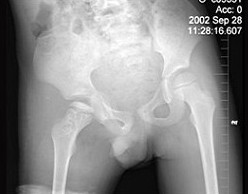

7岁男孩,发现跛行半年伴疼痛,来科行双髋节正位片,如图所示,最佳的诊断是()

A:右髋关节结核

B:右股骨头骨软骨炎

C:右侧扁平髋

D:克丁病

E:右髋关节肿瘤